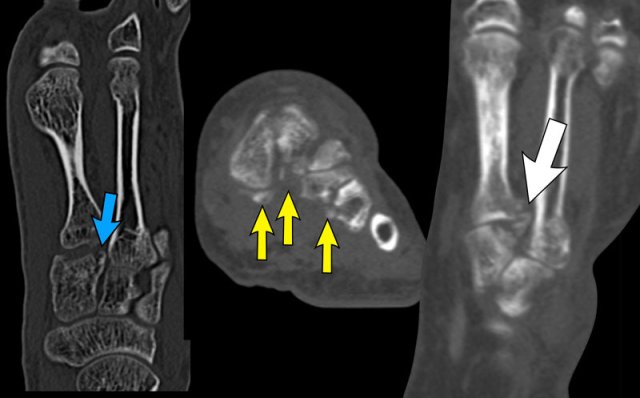

On the CT we see a coalition between the calcaneus and the os naviculare.

The CT shows sclerosis and subchondral cysts as a sign of ‘friction’ due to the neoarticulation.

The MRI shows bone marrow edema as a sign of a symptomatic coalition.